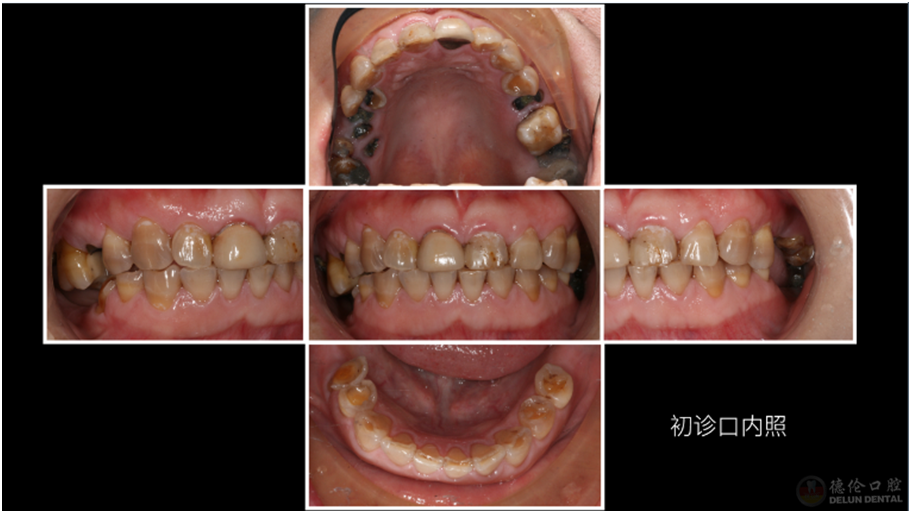

患者症状:牙齿龋坏、四环素牙、牙齿缺失。

治疗方法:治疗牙髓炎和根尖周炎的患牙、拔除残根残冠、升高咬合,种植修复及全冠修复。

术前: